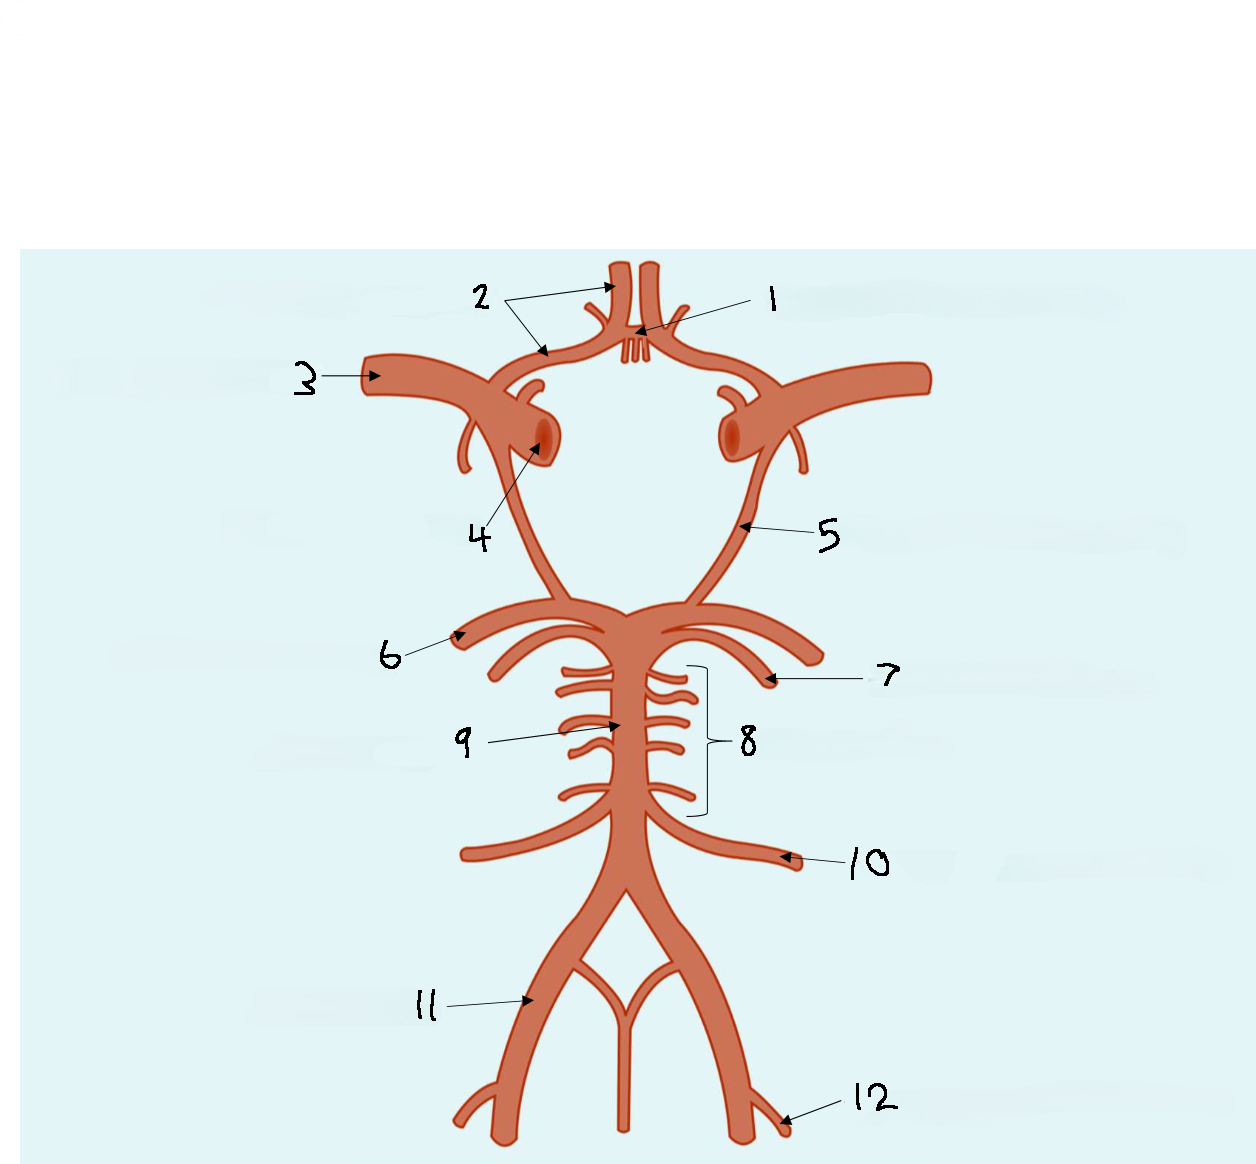

What is 1?

anterior communicating artery

What is 2?

anterior cerebral artery

What is 3?

middle cerebral artery

What is 4?

internal carotid artery

What is 5?

posterior communicating artery

What is 6?

posterior cerebral artery

What is 7?

superior cerebellar artery

What is 8?

pontine arteries

What is 9?

basilar artery

What is 10?

anterior inferior cerebellar artery

What is 11?

vertebral artery

What is 12?

posterior inferior cerebellar artery